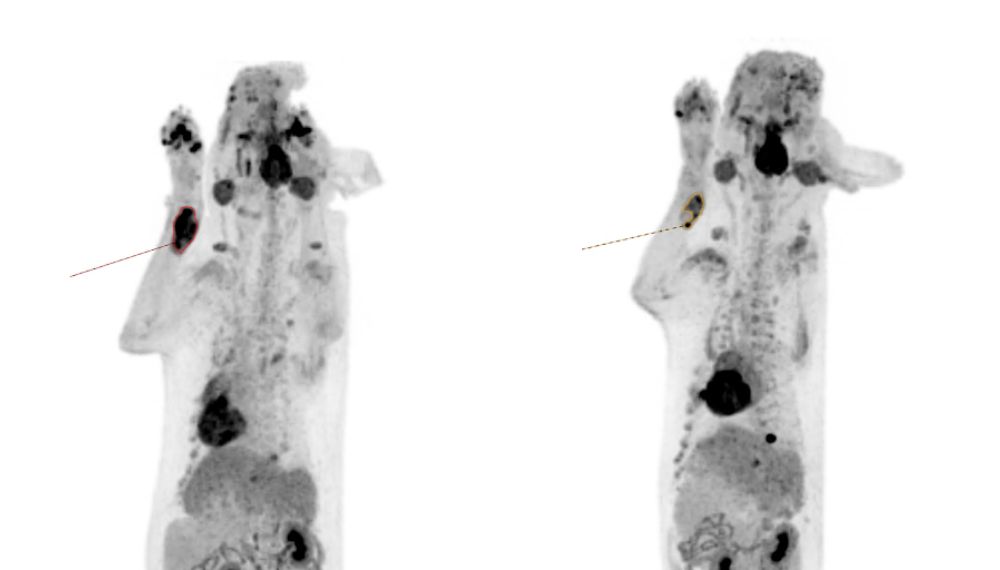

Positron Emission Tomography (PET) is a molecular imaging technique that uses tiny amounts of radioactive tracers to show how the tissues are functioning, such as metabolism, receptors, and blood flow, not just what they look like. The technology is used in human cancer diagnostics and is now available in veterinary medicine.

Oncology (cancer) is the number one application for PET-CT scans in veterinary practice.

- Staging & restaging: Find metastases that may be invisible on CT/US, refining stage and prognosis.

- Therapy planning: PET/CT helps delineate biologic tumour volumes for radiation therapy; dose can be escalated to the most active subregions (“dose painting”).

- Response assessment: Early metabolic changes on PET often precede size changes on CT, which is helpful for chemotherapy/targeted therapy decisions.

A PET-CT scan combines two powerful technologies — Positron Emission Tomography (PET) and Computed Tomography (CT) — to show the structure and function of tissues. It uses molecular tracers to detect disease activity at a cellular level, revealing information invisible to standard imaging. PET-CT is especially valuable in cancer diagnosis, staging, treatment planning, and monitoring, helping vets understand how the disease behaves inside the body.